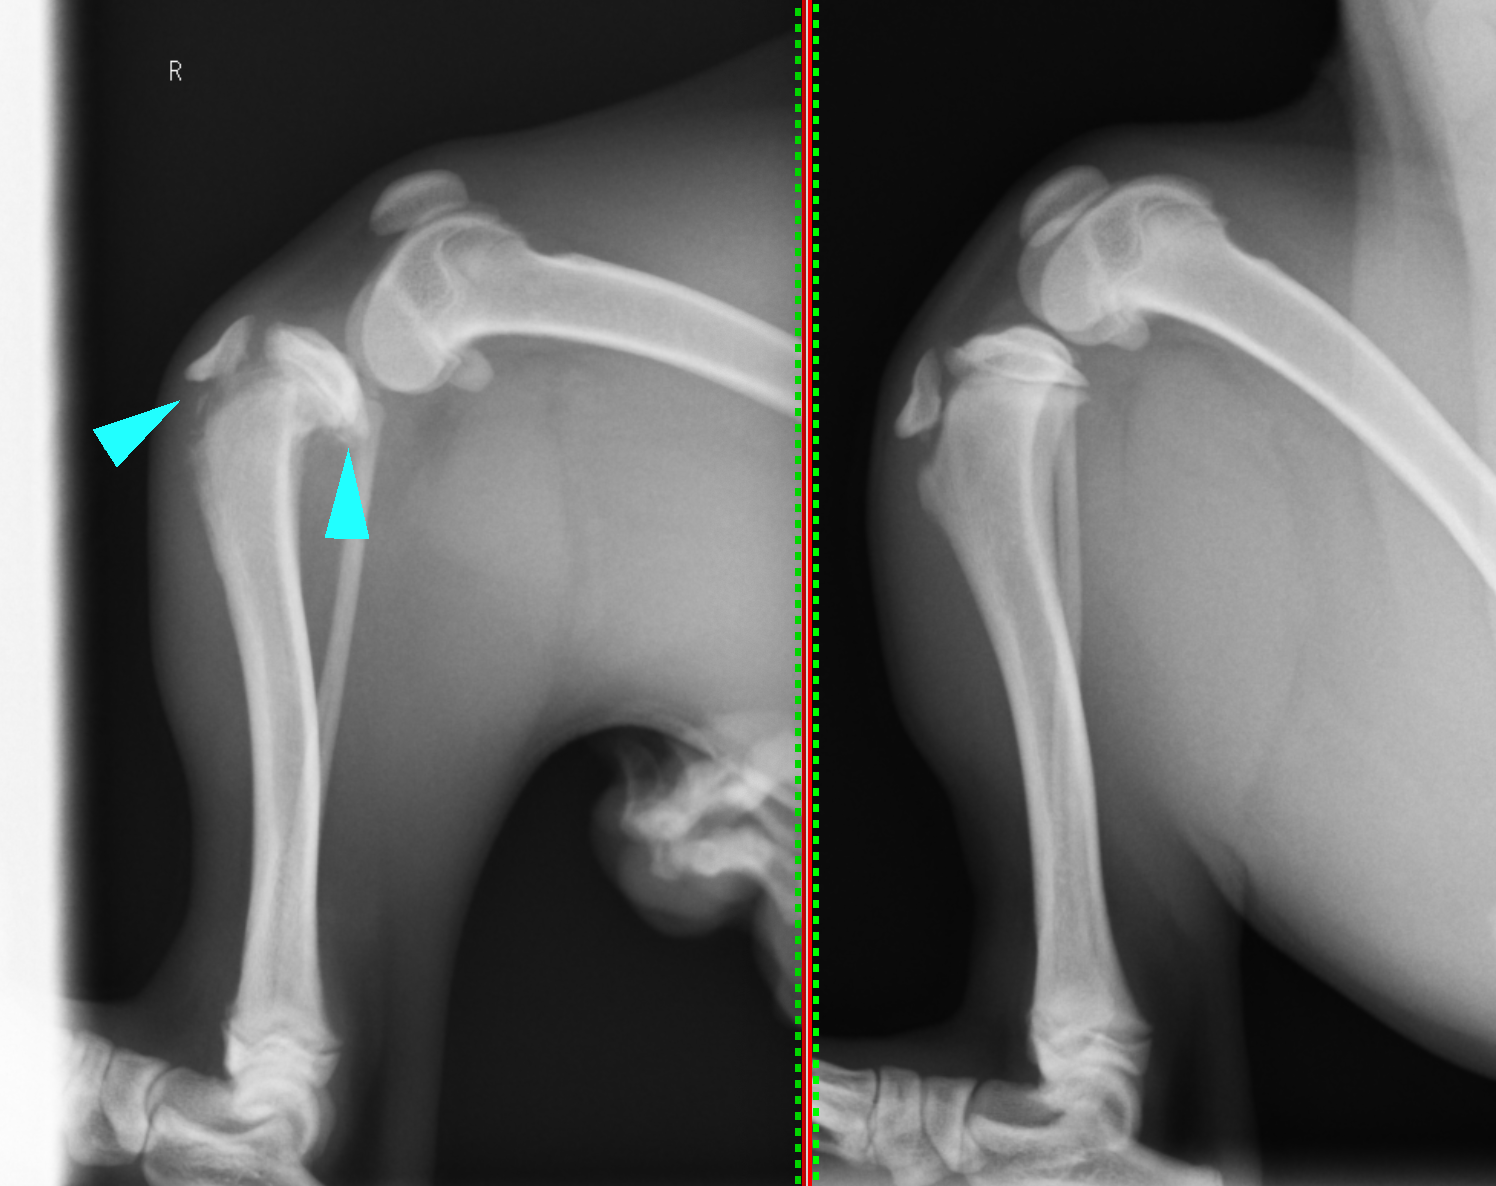

脛骨粗面剥離骨折 東京都町田市の二次診療動物病院 オールハート動物リファーラルセンター

脛骨剥離骨折整復手術 ピン ワイヤー固定 かみや動物クリニック

脛骨粗面の剥離骨折 整形外科 やまと動物病院

犬の脛骨粗面の剥離骨折 整形外科 やまと動物病院

とりい動物クリニック 静岡県富士市 成長期のワンちゃんにある骨折 脛骨粗面の剥離

脛骨粗面剥離骨折 アレス動物医療センター